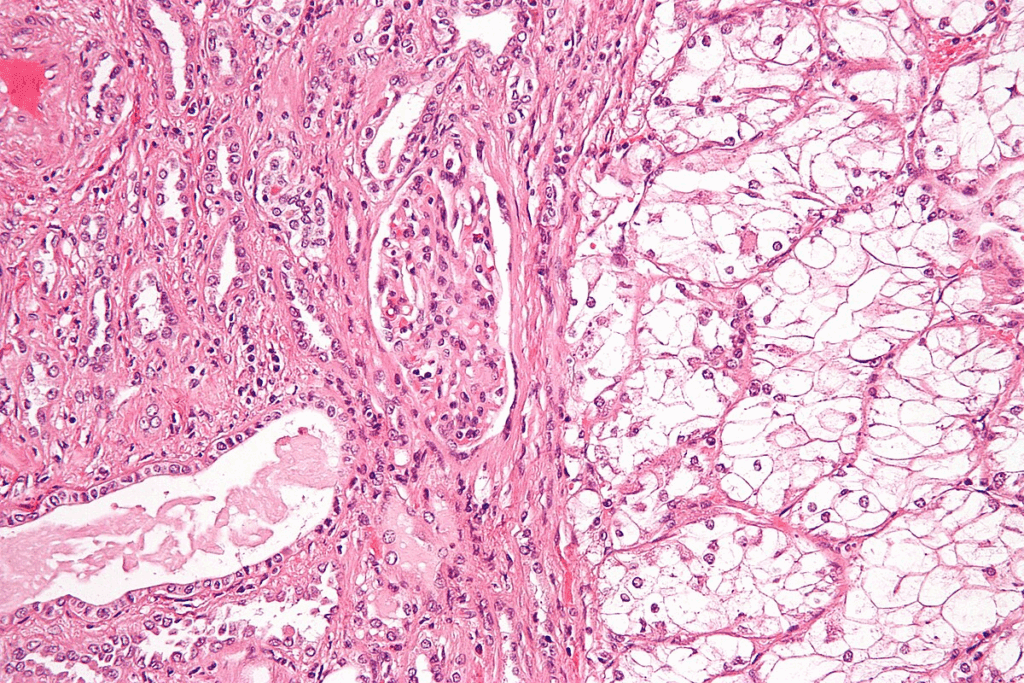

The Cellular Transformation Process

It’s key to grasp the cellular transformation process for better cancer prevention and treatment. This process happens when normal cells get genetic mutations. These mutations mess up how cells work normally.

Normal Cell Growth vs. Cancerous Growth

Normal cell growth is tightly controlled. It ensures cells divide, grow, and die properly. But, cancerous growth is out of control. It leads to cells growing too much, losing their shape, and not dying when they should.

Genetic mutations are the main difference between normal and cancerous growth. These mutations can come from many sources. This includes harmful substances in the environment, genetic traits, and viruses.

Stages of Cellular Transformation

The transformation of cells goes through several stages:

- Initiation: This is the start where genetic changes happen due to different causes.

- Promotion: Here, these changes get stronger, leading to pre-cancerous growths.

- Progression: The last stage where these growths turn into invasive cancer.

Knowing these stages helps us find ways to stop or treat cancer more effectively.